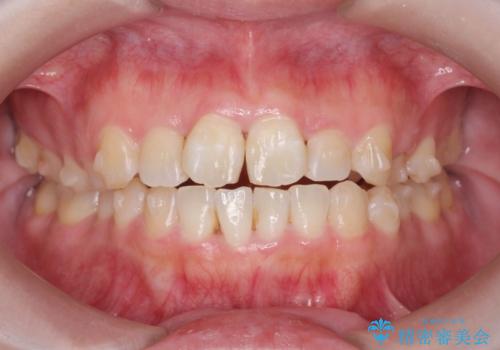

前歯のねじれをマウスピース矯正インビザラインで治療

- 長年気になっている、前歯のねじれの矯正治療を希望され来院されました。

十分にマウスピース矯正インビザラインで治療が可能と判断し、治療を進めることとしました。

長年気になっていた前歯のねじれが、ワイヤーをつけることなく矯正を行うことができ、大変喜んでいただくことができました。